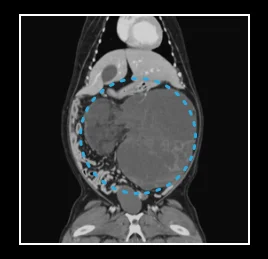

• 복부 질환

간 종양, 비장 종양, 신장 종양, 소장 종양,

• 간 종양

• 비장 종양